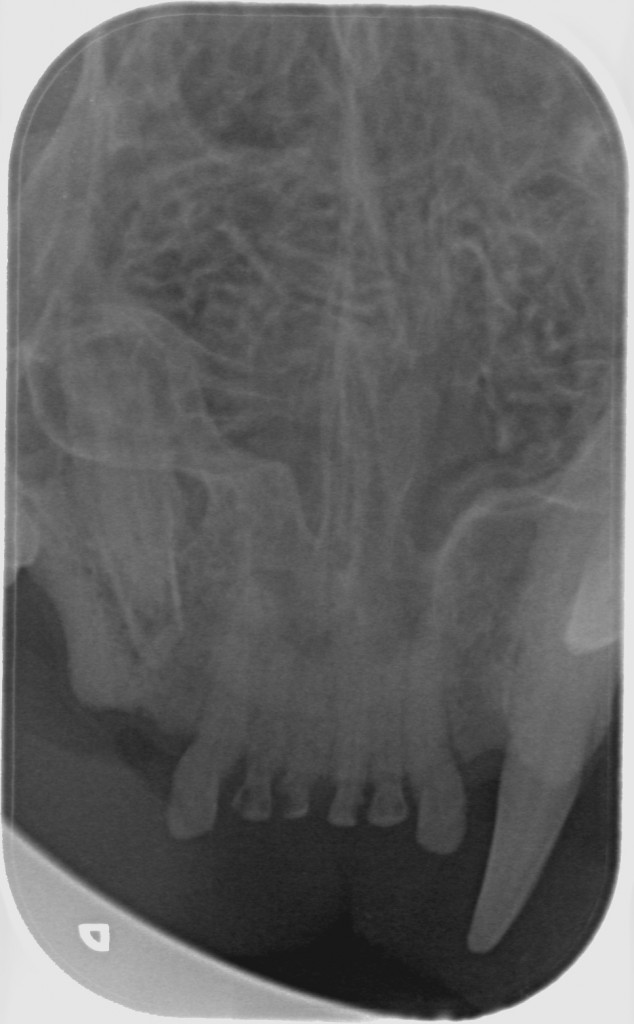

Tænder med TR skal trækkes ud. Men alligvel er det nødvendigt at tage tandrøntgen af alle tænderne for at se om der er andre tænder, der er angrebet af TR.

Det eneste man som katteejere kan gøre er at få sin kat undersøgt for TR mindst en gang årligt i forbindelse med det årlige tjek hos dyrlægen. Din dyrlæge kan henvise til speciallæger, der foretager tandrøntgen, men du kan også selv henvende dig til en specialdyrlæge, der foretager tandrøntgen af katte.

På Dyretandspecialist kan du læse mere om sygdommen Tooth Resorption (TR/FORL) hos katte. Her kan du både se røntgenbilleder og billeder af tandsygdommens stadier, samt se symptomerne på sygdommen, så du ved, hvad du skal være opmærksom på hos din kat.

Nedenfor kan du se de 8 røntgenbilleder af Shana-Mio´s tænder, som specialtanddyrlægen tog af hendes tænder i 2008, da hun fik konstateret TR/FORL: